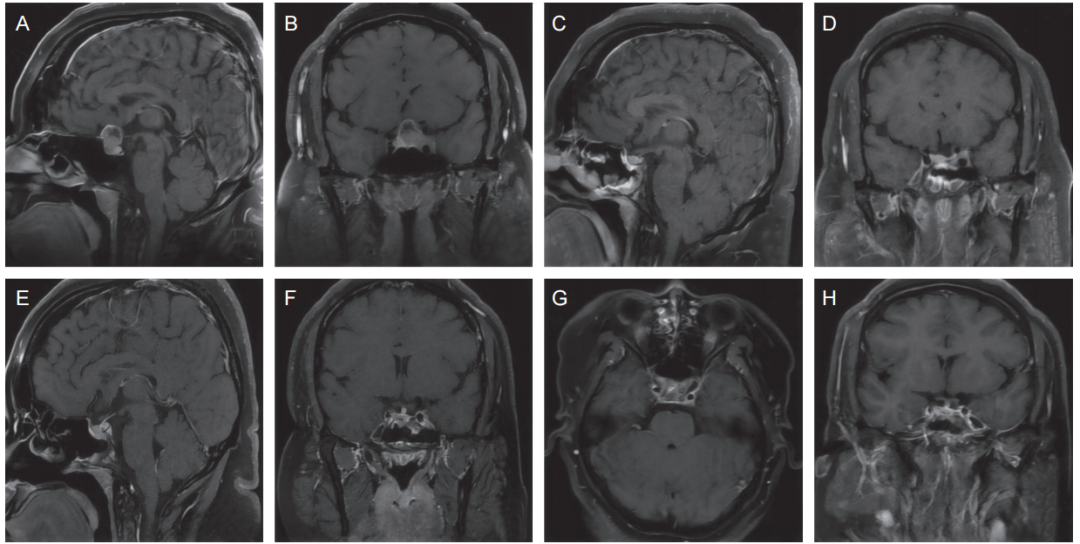

图1 垂体腺瘤继发性头痛病人垂体及颅脑磁共振成像

术前垂体磁共振平扫+动态增强 (A, B) 示鞍区占位,蝶鞍扩大,鞍底下陷,病变边界不清,增强呈轻度异常强化,视交叉受压上抬,病灶累及左侧海绵窦;术后3个月复查垂体磁共振+动态增强 (C, D) 示垂体腺瘤术后改变,蝶窦炎;术后7个月复查垂体增强磁共振 (E, F) 及颅脑增强磁共振 (G, H) 示垂体左翼区及左侧海绵窦区异常信号并强化,包绕邻近颈内动脉,较前范围略增大,蝶窦炎。

女性,35岁,2024年10月病人无诱因出现双侧枕部、太阳穴及乳突撕裂样疼痛,数字分级评分法 (NRS) 8~9 分,伴双侧耳鸣、视物模糊,就诊于中国人民解放军总医院第一医学中心神经内科。垂体MRI平扫+动态增强提示垂体腺瘤(见图1A, 1B)。

2025年2月27日(术后3个月)复查垂体MRI平扫+动态增强提示垂体腺瘤术后改变、蝶窦炎(见图1C, 1D)。口服普瑞巴林、奥沙西泮、加巴喷丁等药物后头痛略有缓解,后加用度洛西汀、阿米替林等药物及枕大神经阻滞治疗,症状改善不明显。

2025年6月20日(术后7个月)病人于我科住院治疗,入院时入睡困难,夜间易醒,多梦,体型肥胖,体重指数 42.1 kg/m2。腰椎穿刺示脑脊液压力160 mm液柱,脑脊液常规、生化、免疫、白细胞介素检测均未见明显异常。复查垂体增强MRI(见图1E, 1F)及颅脑增强MRI(见图1G, 1H)提示垂体左翼区及左侧海绵窦区异常信号并强化,包绕邻近颈内动脉,较前范围略增大。病人既往于18年前因压力大曾有枕部持续性头痛病史,NRS 7~8分,服用中药(具体不详)后头痛消失。糖尿病病史5年。内科查体无异常。神经系统查体见左侧枕大、枕小神经及双侧耳颞神经出口处按压痛,口周针刺觉过敏,余神经系统查体未见明显异常。

术前垂体MRI平扫+动态增强示:鞍区占位,考虑垂体腺瘤(见图1A, 1B)。

术后3个月复查垂体MRI平扫+动态增强示:垂体腺瘤术后改变,蝶窦炎(见图1C, 1D)。

术后7个月复查垂体增强MRI(见图1E, 1F)及颅脑增强 MRI(见图1G, 1H)示:垂体左翼区及左侧海绵窦区异常信号并强化,包绕邻近颈内动脉,较前范围略增大。